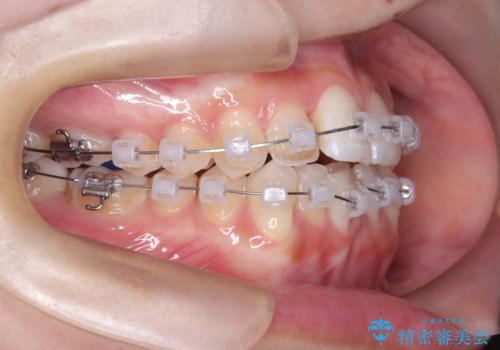

- 矯正装置

- クリア装置 ワイヤー

治療計画をしっかり立て、歯の移動量や力のコントロールを最適化することで、約1年という短期間で矯正治療を終了することができました。

「矯正は時間がかかる」というイメージをお持ちの方も多いですが、症例によっては、非抜歯でも短期間で改善が可能な場合があります。